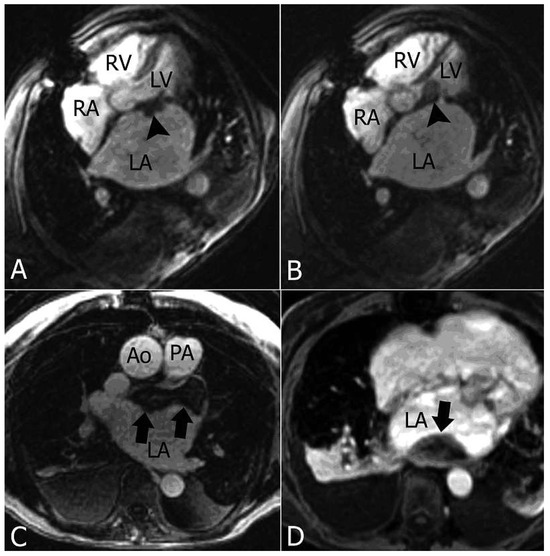

Primary Left Atrial Angiosarcoma Determining Severe Mitral Valve Stenosis

by Natalia Pavone, Vasileios Tsiopoulos, Riccardo Marano, Mariangela Novello and Mario Gaudino

Cardiovasc. Med. 2012, 15(2), 55; https://doi.org/10.4414/cvm.2012.01642 - 22 Feb 2012

Primary cardiac tumours are a rare pathogical entity. In the vast majority of cases these tumours are benign [1,2]; among malignant histotypes, angiosarcoma is the most common, representing 15–35% of all cardiac tumours [2,3]. Primary cardiac angiosarcomas usually arise from the right atrium [...] Read more.

Primary cardiac tumours are a rare pathogical entity. In the vast majority of cases these tumours are benign [1,2]; among malignant histotypes, angiosarcoma is the most common, representing 15–35% of all cardiac tumours [2,3]. Primary cardiac angiosarcomas usually arise from the right atrium or the pericardium; they typically occur in the third to fifth decade of life and are two to three times more frequent in males. We report a case of primary angiosarcoma arising from the left atrium in a female patient who had already undergone mitral valve repair. Full article

Show Figures

Figure 1